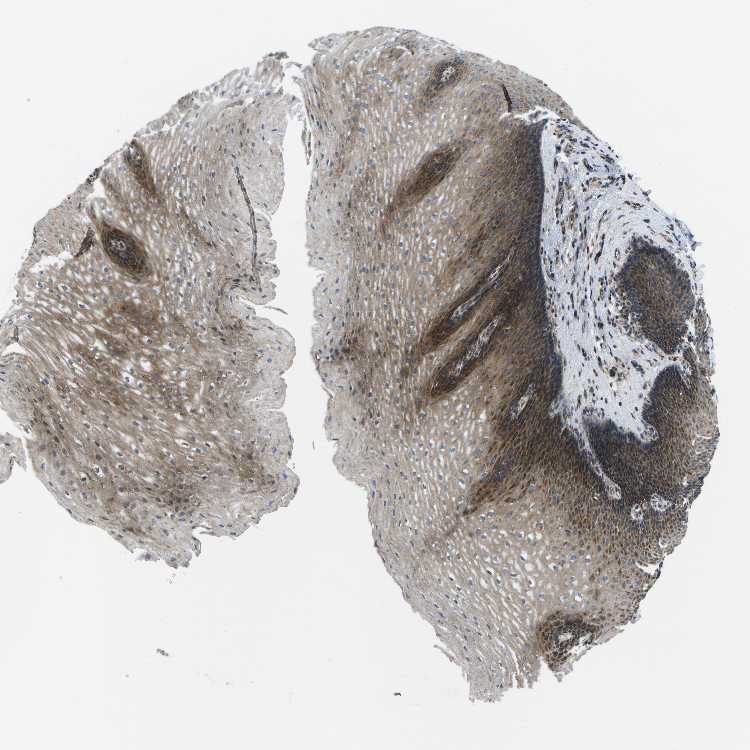

ESOPHAGUS - Antibody stainingi

Antibody staining in the annotated cell types in the current human tissue is reported as not detected, low, medium, or high, based on conventional immunohistochemistry profiling in selected tissues. This score is based on the combination of the staining intensity and fraction of stained cells.

Each image is clickable and will lead to virtual microscopy that enables deeper exploration of all samples and also displays staining intensity scores, fraction scores and subcellular localization as well as patient and tissue information for each sample.

Antibody HPA016961

Squamous epithelial cells High